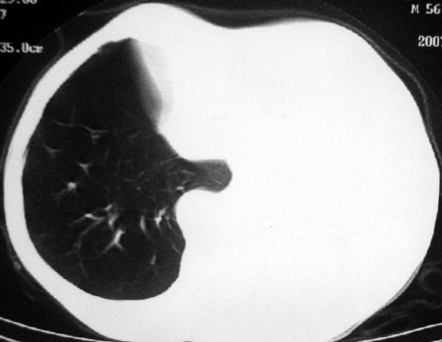

男,54岁,咳嗽,气喘半年,胸痛一月.

血性胸水

左肺下叶中心型肺癌,伴阻塞性肺炎、左胸腔积液、心包少量积液。

1.左肺下叶中心性肺癌伴阻塞性肺炎,肺不张.

2.左侧胸腔积液,心包积液